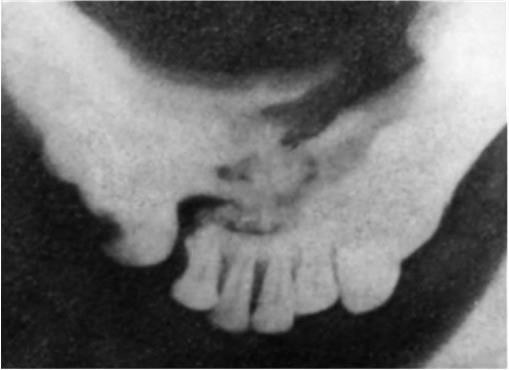

Иногда для получения рентгеновского изображения височнонижнечелюстного сустава прибегают к укладкам по Шюллеру и Пордесу, а для того, чтобы получить представление о ходе щели перелома в подбородочном отделе, делают внутриротовой снимок: пленку помещают между зубами нижней и верхней челюсти, а тубус аппарата направляют на срединную часть подбородка снизу. Комплексное рентгенологическое обследование позволяет уточнить клинические данные о локализации перелома, направлении и степени смещения отломков (рис. 3).

Рис. 3. Отпечаток с рентгенограммы подбородочного отдела нижней челюсти «на прикус». Отчетливо определяется перелом тела челюсти на уровне передних зубов